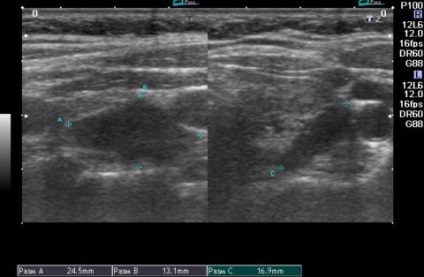

Annak érdekében, hogy meghatározzuk, mekkora mennyiség változott mellékpajzsmirigy szöveteinek, a következő képletet: V mellékpajzsmirigy (cm3) = π / 6hAhBhC, ahol A, B és C - a test méreteinek hüvelykben. Ha glandulae parathyroideae térfogata akár 0,5 cm3, ők tekinthetők, hogy kicsi, és ha több, mint 0,5 cm3, majd - nagy.

Meghatározása egy ultrahangos belső áramlási csak akkor lehetséges, növeli a test mérete (32% az esetek másodlagos paraméterek 21H10 milliméter).

A normális állapotban, ezek az endokrin szervek ultrahang jelennek homogén hypoechoic ovális vagy lekerekített sima képződése szempontjából tiszta kontúrokkal, bármilyen mennyiségben legfeljebb 30 mm, amelyek vannak elhelyezve a felső és alsó pólusa a pajzsmirigy hátsó fal. Erezettség mellékpajzsmirigy a legtöbb esetben hiányzik.